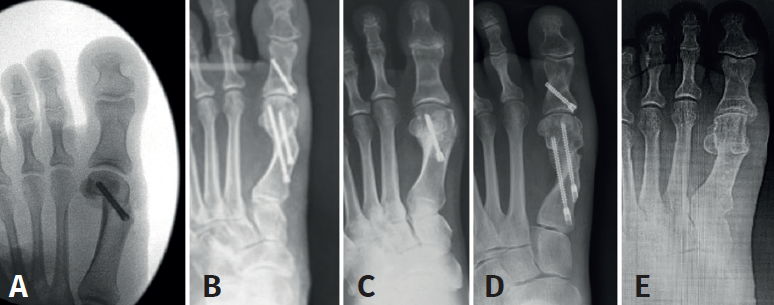

Mediante abordaje de 5 mm a nivel plantar proximal al bunion se realiza capsulotomía y exostectomía (Figuras 1A, B y C). Por otro abordaje de 3 mm realizado a 5 mm dorsal y distal del primero y a 15 o 20 mm proximal a la superficie articular (entre 7 y 10 mm del centro geométrico de la cabeza), extraarticular y equidistante a la cortical dorsal y plantar, se procede al tallado de la osteotomía de Chevron con fresa Isham larga (2,0 × 12 × 65 mm), (Figura 1D). Con la fresa dirigida, preferentemente, perpendicular al cuarto metatarsiano y llevándola ligeramente a plantar o dorsal según quisiéramos descender o elevar, respectivamente, la cabeza metatarsiana, perforamos el primer metatarsiano. En modelos sin fijación, elegimos esta dirección hacia proximal para lograr un leve acortamiento, que relaja la articulación metatarsofalángica y reduce las posibilidades de pérdida de corrección de la cabeza (Figura 2). En modelos con fijación se dirige más hacia distal, con referencia en la diáfisis del segundo metatarsiano o incluso perpendicular al primer rayo. Realizamos el corte dorsal casi vertical y el corte plantar lo más horizontal posible (paralelo al suelo), con dirección de distal a proximal, tratando de que esta rama sea más larga que la anterior. Se puede lograr de forma adicional corrección del DMAA. Una vez completa la osteotomía, se desplaza a lateral manualmente bajo visión radioscópica hasta que se logra una posición satisfactoria. No se coloca osteosíntesis. Se procede a la adición de otros gestos percutáneos de ser necesarios (liberación lateral de partes blandas, osteotomía de Akin, osteotomías de metatarsianos o dedos menores) (Figura 3).

Los estudios y/o técnicas mínimamente invasivas relevantes sobre Chevron percutánea con fijación son: PeICO (Del Vecchio et al.), PERC (Hernández et al.), PECA (Lee et al.), MICA (Redfern-Vernois)(6,18,19).

Del Vecchio, en una primera publicación donde evalúa el resultado radiográfico de la técnica PeICO (percutaneous, intra-articular, Chevron osteotomy), concluye no encontrar acortamiento del primer metatarsiano ni recurrencias, y corrección satisfactoria de los valores angulares. En una segunda publicación más actual y de estudio cadavérico arroja que esta técnica es segura, no encontrando daños vasculonerviosos o tendinosos; utiliza un tornillo de fijación sin atravesar la cortical lateral y es reproducible en cirujanos experimentados en técnica MIS de pie, imitando el Chevron abierto.

Una MICA (minimally invasive Chevron Akin) es una técnica que se aleja del centro geométrico de la cabeza hacia proximal, es extraarticular, se realiza en el cuello del metatarsiano, utiliza 2 tornillos sin cabeza de fijación y se asocia con una osteotomía de Akin. Sus autores publican buenos y excelentes resultados, sin rigidez metatarsofalángica y extienden la indicación hasta el hallux valgus grave, ya que proponen hasta un 100% de desplazamiento de la cabeza metatarsiana.

Una PERC (percutaneous extra-articular reverse-L Chevron osteotomy) realiza la osteotomía en el mismo sitio que la MICA, pero la diferencia es que fija con 1 tornillo de dorsal a plantar.

Una PECA (percutaneous Chevron/Akin) es técnicamente lo mismo que la MICA.

Como vemos, la sugerencia de algún tipo de estabilización debido al riesgo de desplazamiento de la cabeza metatarsiana, menor dolor y edema es una constante en las mencionadas publicaciones. Este concepto es discutible debido a que la osteotomía de tipo Chevron realizada con la rama plantar larga y paralela al piso es intrínsecamente estable y compatible con un postoperatorio de carga precoz (Figuras 4A, B y C) al igual que las osteotomías “con fijación”(17). Los problemas relacionados con el uso de osteosíntesis en las osteotomías metatarsianas ascienden al 10-15% en diferentes series(3,9,11).

Las complicaciones asociadas con el Chevron incluyen la necrosis avascular(1,12). En nuestro trabajo no hubo casos y creemos que esto se debe a que, al realizar los gestos de forma percutánea y más proximales, Chevron + abductor + Akin, el daño vascular es menor. Esto también explicaría que las osteotomías tengan un alto porcentaje de consolidación (Figura 6).

Nuestro modelo PECU puede hoy ser comparado con series con fijación, arrojando resultados similares(2,9,10,11,12,13)(Figura 7).